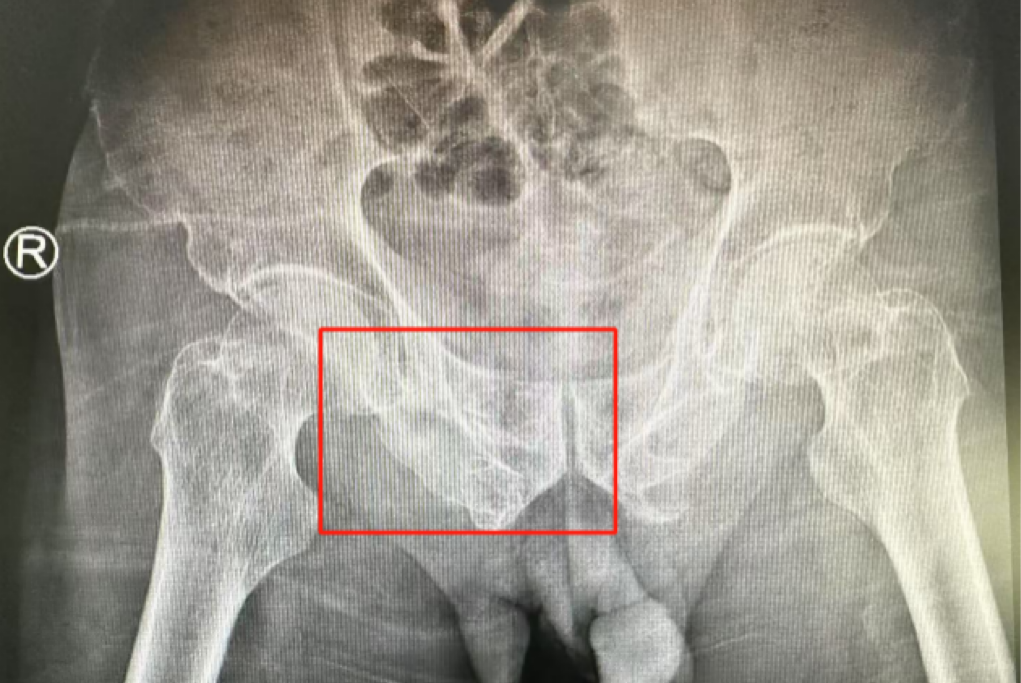

ÊõǰӰÏñѧÏÔʾ£¬»¼ÕßµÄ×ó²à÷¾¹Ç¹ÇÕÛ£¬ÓÒ²à³Ü¹Ç¹ÇÕÛ¡¢÷ĹǹÇÕÛ£¬¹ÇÅè¹ÇÕÛ·ÖÐÍΪCÐÍ£¬ÍíÄê´àÐÔ¹ÇÅè¹ÇÕÛ·ÖÐÍΪIVÐÍ£¬ÊǼ«¶Ë²»ÎȹÌÐ͵Äǰ»·¹ÇÕÛºÍË«²àºó»·¹ÇÕÛ¡£ËùÐÒûÓÐÏÔ×ŵĹÇÅè³öѪ»òÄÚÔàËðÉ˵ÄÌåÏÖ¡£

Âݶ¤Ö²ÈëλÖúÜÊÇÖª×ã